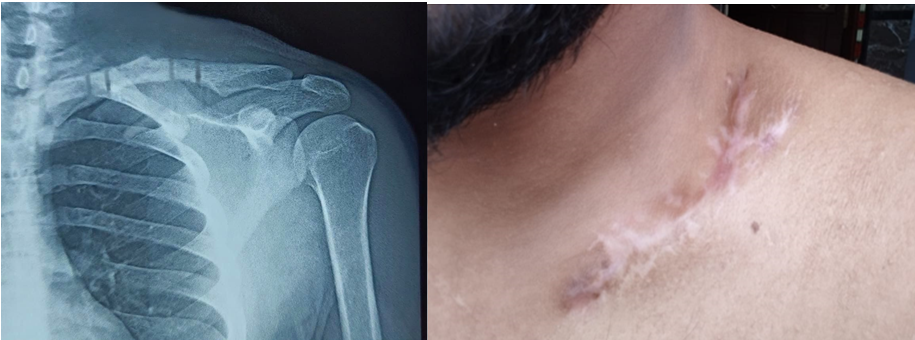

- Week 4- Physiotherapy continued and no signs of pin tract infection noted (Fig. 4)

Figure 4: Post-operative X-ray and local skin condition at 3 weeks post-operative.

- Week 6- Radiological signs of uniting clavicle fracture with satisfactory alignment noted

- Week 12- United clavicle fracture on X-ray and LCP External fixator removed,

- No discharge/pin tract infection (Fig. 5)

Figure 5: Post-operative X-ray at 3 months demonstrating good bony union and completely healed surgical scar post ex-fix removal .